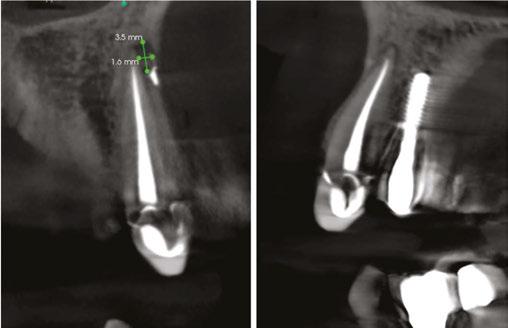

As previous literature has identified the negative effect between periradicular periodontitis of natural teeth and adjacent implants, a limited field of view CBCT (Carestream Dental S 8200 3D, Atlanta, Georgia) was exposed to properly define the periapical radiolucency. Measuring from the apex of tooth No. 11 to a line perpendicular to the long axis of the implant,

Figure 1 (left): Periapical radiograph taken at the time of tooth No. 11 crown delivery in 2018 with a periapical radiolucency extending distally toward implant No. 12. Figure 2 (right): Updated periapical radiograph taken in 2023 during a periodic oral exam showing clear delineation of a periapical radiolucency associated with tooth No. 11

Figure 3: Periapical radiographs taken during endodontic consultation in 2023. Periapical radiolucency originated from tooth No. 11 and extended toward implant No. 12. Calcification was appreciated in the coronal portion of the canal space on tooth No. 11

5A-5B: CBCT was taken during initial endodontic exam in 2023. 5A. Coronal CBCT

revealed a 6.1 mm x 3.0 mm hypodensity extending from the apical and distal aspect of No. 11. 5B. Sagittal

slices revealed the presence of bone between tooth No. 11 and implant No. 12

spacing of 3.4 mm between the two was noted (Figure 4). The recommended amount of space between a natural tooth and dental implant should be 1.5 mm-2 mm, proving adequate spacing in this case.15 Coronal views of the CBCT evaluation revealed a 6.1 mm x 3.0 mm hypodensity extending from the apical and distal aspect of tooth No. 11 (Figure 5A). Sagittal slices revealed the presence of healthy bone morphology between the distal border of the hypodensity on tooth No. 11 and implant No. 12, thus the hypodensity did not extend to the implant (Figure 5B). Reference was made to the Treatment Options for the Compromised Tooth: A Decision Guide published by the AAE in 2017 to determine prognosis.16 In evaluating the coronal tooth structure, tooth No. 11 had a well-fitting crown with adequate margins, no need for crown lengthening, and required only routine endodontic treatment placing it in the favorable category. The periodontal condition of tooth No. 11 was also favorable with probing depths equal to or less than 3 mm and a normal periodontium. Lastly, the apical periodontitis was expected to resolve following non-surgical root canal treatment.16 Thus, tooth No. 11 was diagnosed as pulpal necrosis with asymptomatic apical periodontitis with a favorable prognosis. Nonsurgical root canal treatment was planned, and informed consent was obtained.

Figure 4: Sagittal CBCT slice revealed 3.4 mm of space between the apex of tooth No. 11 and the mesial border of implant No. 12